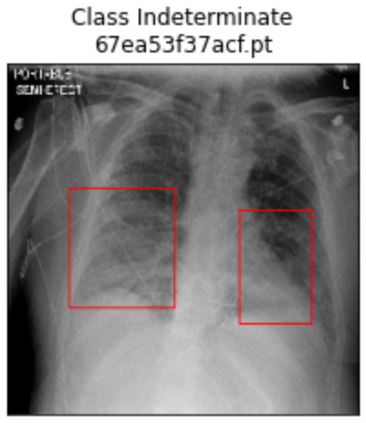

Deep learning technologies have already demonstrated a high potential to build diagnosis support systems from medical imaging data, such as Chest X-Ray images. However, the shortage of labeled data in the medical field represents one key obstacle to narrow down the performance gap with respect to applications in other image domains. In this work, we investigate the benefits of a curricular Self-Supervised Learning (SSL) pretraining scheme with respect to fully-supervised training regimes for pneumonia recognition on Chest X-Ray images of Covid-19 patients. We show that curricular SSL pretraining, which leverages unlabeled data, outperforms models trained from scratch, or pretrained on ImageNet, indicating the potential of performance gains by SSL pretraining on massive unlabeled datasets. Finally, we demonstrate that top-performing SSLpretrained models show a higher degree of attention in the lung regions, embodying models that may be more robust to possible external confounding factors in the training datasets, identified by previous works.